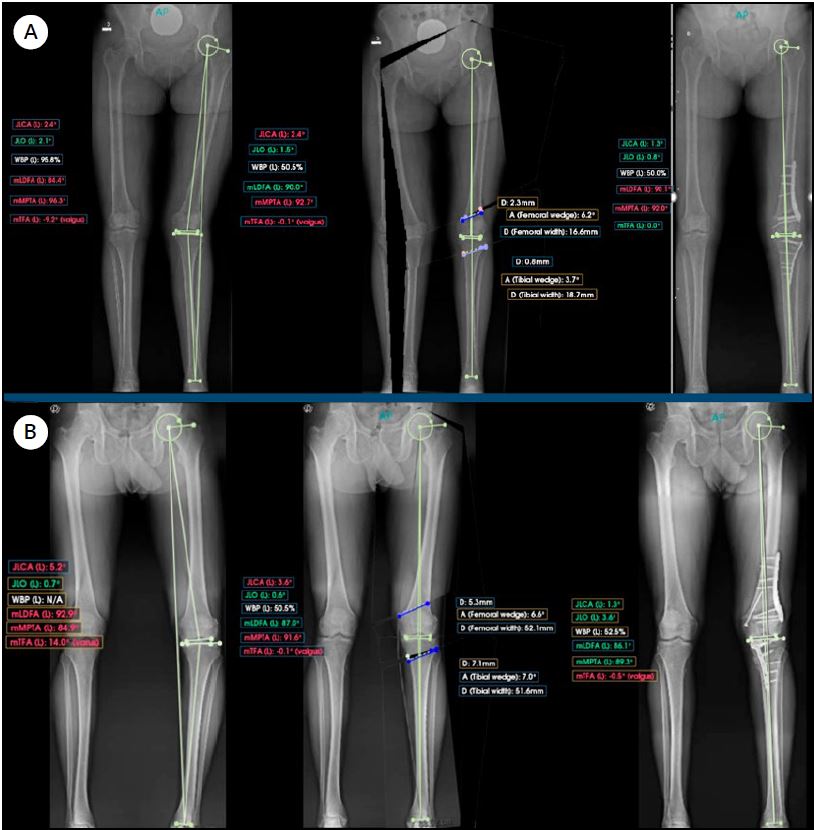

La planificación digital se efectúa utilizando PeekMed® (software de planificación digital asistido por inteligencia artificial para alineación mecánica y corrección angular), con el objetivo de restablecer una alineación mecánica neutra y ángulos articulares normales (Fig. 1).

Figura 1. Planificación digital pre y postoperatoria. Se observa la corrección del eje mecánico y la restauración de los parámetros articulares normales mediante PeekMed®. A) Deformidades en valgo. B) Deformidades en varo.